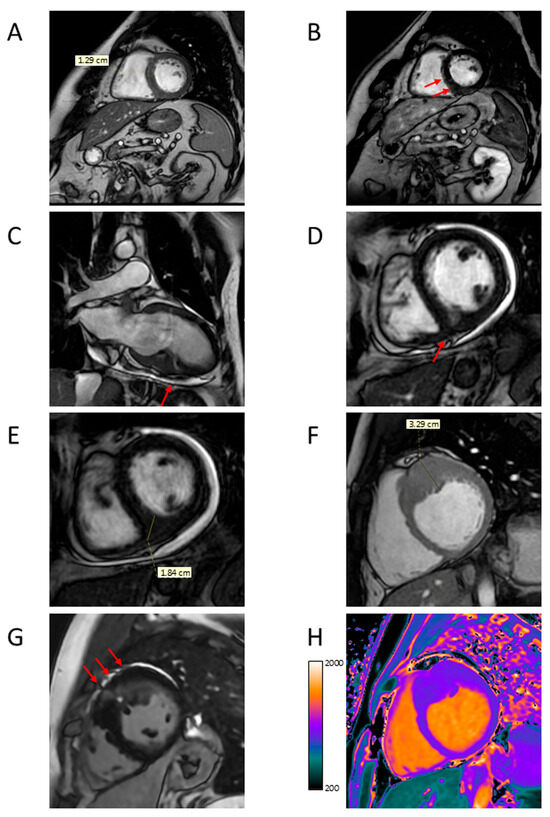

4.2. Apical Aneurysm

4.3. LVOTO

4.4. LV Function

4.5. Myocardial Fibrosis

4.6. Microvascular Dysfunction